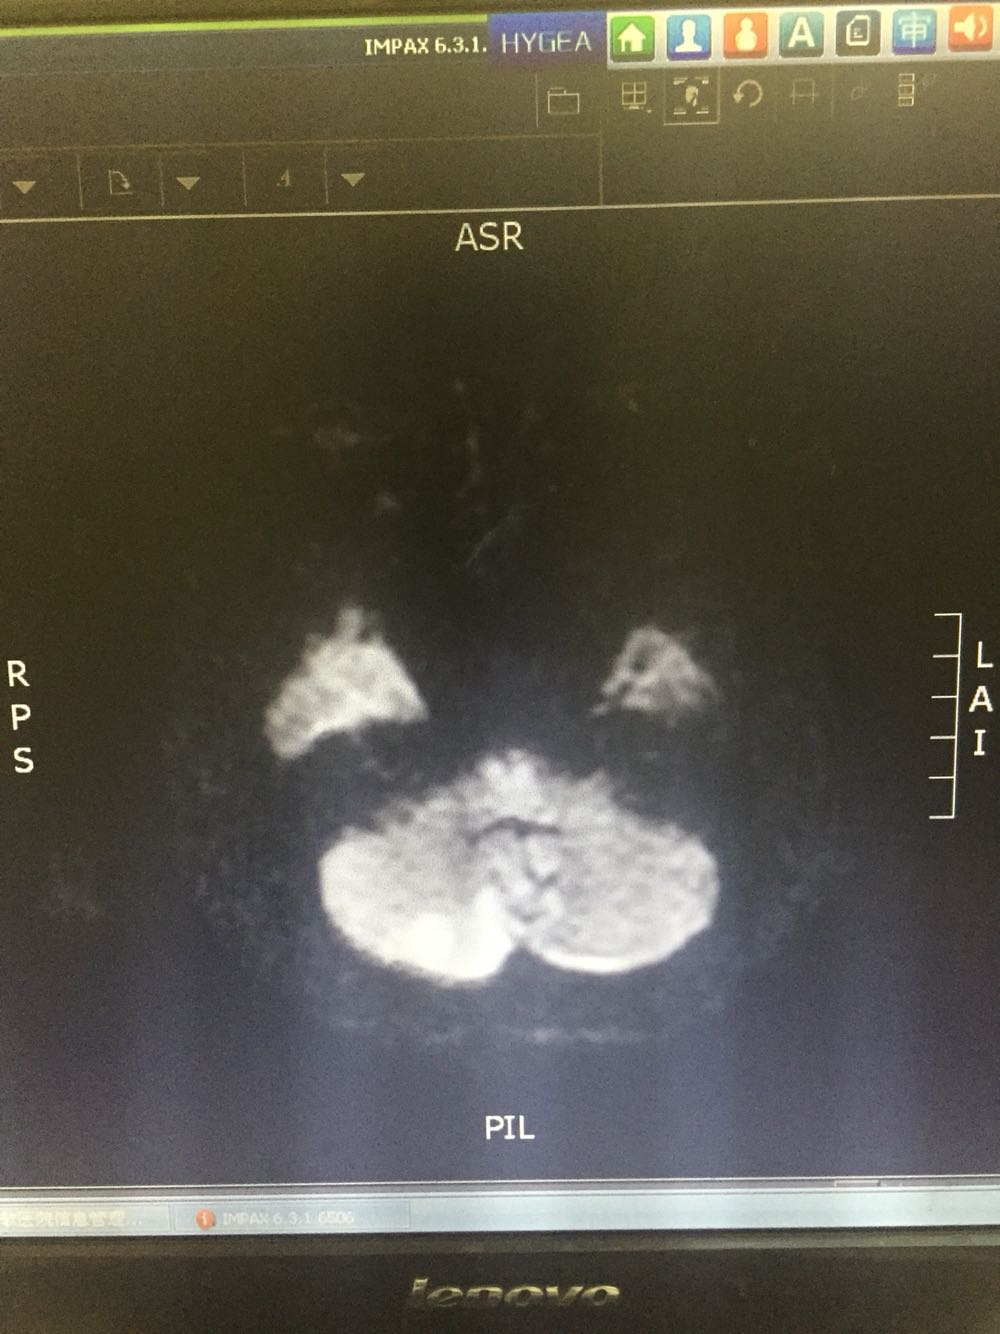

76岁女患,因眩晕三小时入院 既往高血压3年,冠心病史 该患者于入院前三小时无明显诱因出现眩晕,伴有恶心、头痛,无呕吐,病程中无肢体活动障碍,无言语不清,无意识障碍及尿便失禁,不伴有耳鸣及听力减退,为求进一步诊治而来我院。 血、尿化验未见明显异常

诊断:脑梗死、高血压 治疗:改善循环、抗血小板聚集、营养神经、调控血压对症治疗

主要注意与基地动脉尖综合症相鉴别。该患者右侧P2及左侧P3段局限性狭窄